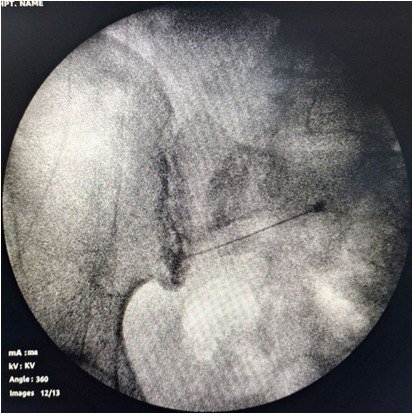

• Imaging-guided targeting: Fluoroscopy or ultrasound helps the doctor visualize the exact structure causing pain.

• Precise treatment delivery: Medication to reduce inflammation,Heat energy for nerve ablation (RFA), Electrical stimulation (nerve modulation)